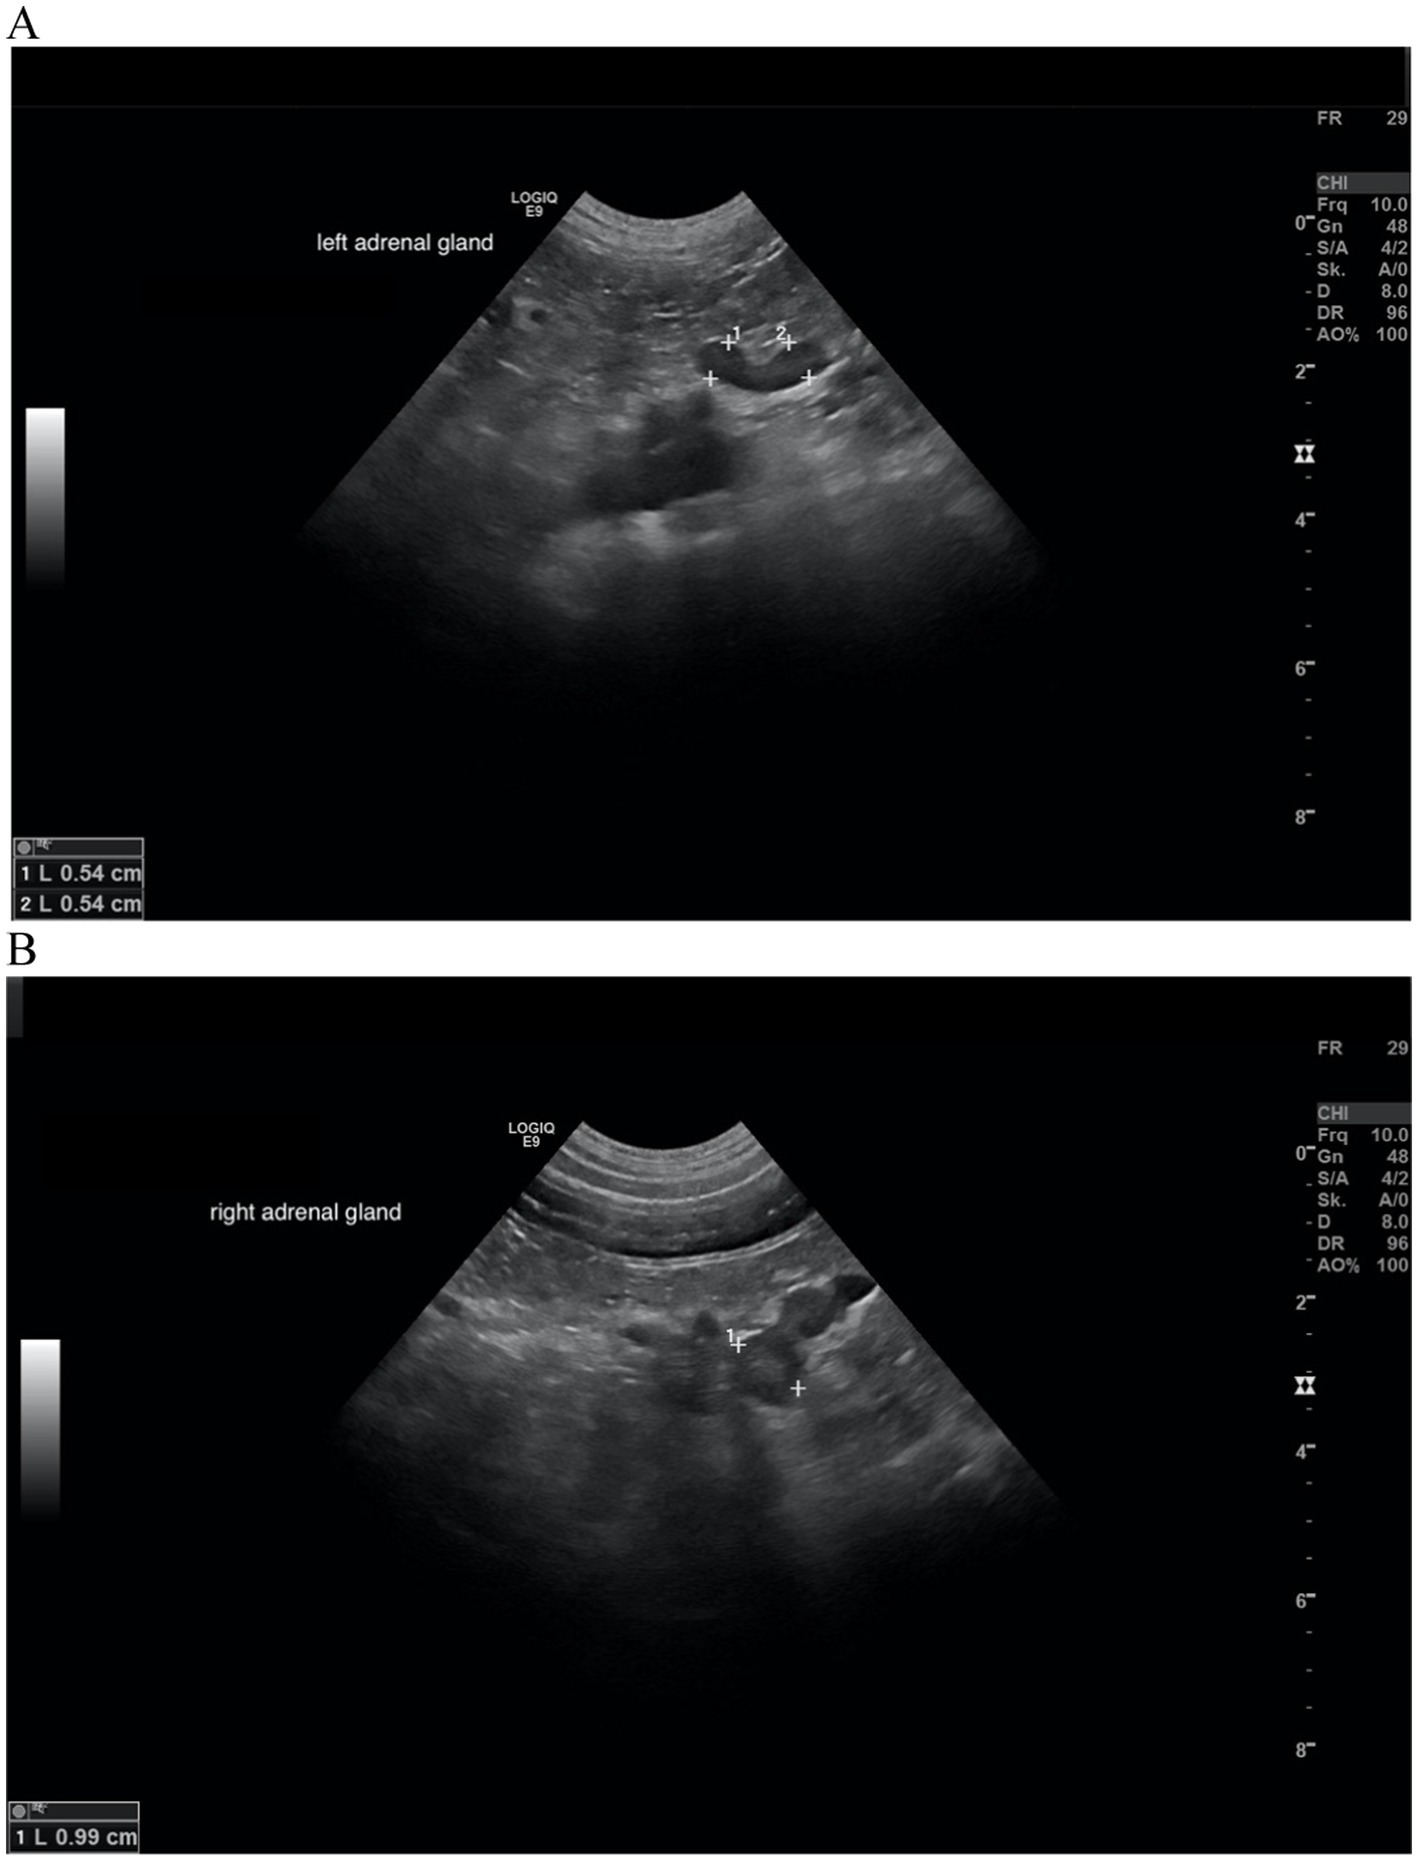

Figure 6

www.frontiersin.org

Figure 6. Ultrasound images of the left and right adrenal gland in a dog with adrenal asymmetry. (A) Cranial and caudal pole of the left adrenal gland measured both 0.54 cm in width. (B) cranial and caudal pole of the right adrenal gland measured 0.99 and 0.74 cm in width. In this dog, no reevaluation of the adrenal glands was performed. MRI had revealed a pituitary macrotumor.

Follow-up was available in 7 of the 9 dogs with a DVTDR >0.3. Follow-up ultrasonography of the adrenal gland was available in 5 dogs (after 3–18 months under therapy with trilostane).

In all 5 dogs with sonographic follow-up, the DVTDR decreased (0.79 → 0.43; 0.52 → 0.08; 0.60 → 0.46; 0.33 → 0.19; 0.72 → 0.66; Table 10). In the other two, one dog had an ultrasound of the urinary tract after 18 months, but the adrenal glands were not addressed in the report, and the other dog was diagnosed with a pituitary macrotumor by MRI after 5 months (Figure 6).